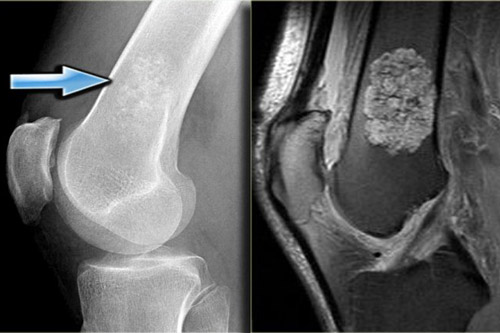

Рентгенограмма, МРТ, сцинтиграфия при энхондроме